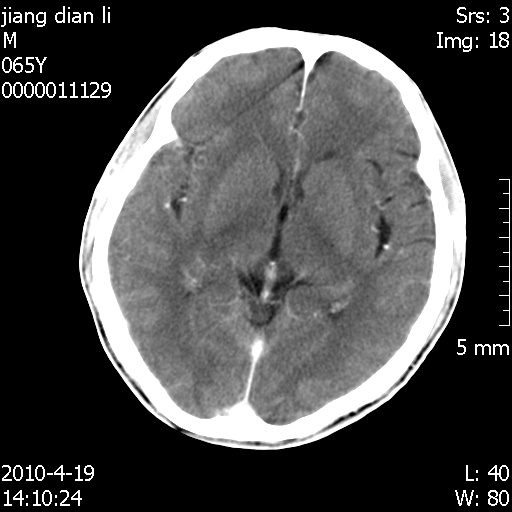

老年男性,突发左下肢无力1天,其余有价值的检查都没有。平扫ct值大约60hu,增强后ct值没什么改变,请大家讨论一下这个病例是什么?说明诊断理由。

今天上班后发现病人前天复查(4月18日发病,19日初诊,22日复查),三个病灶均明显增大,边缘仍旧清楚,水肿加重,右侧脑室基本闭塞。

遗憾! 复习了复查片:发现顶叶出血灶破入侧脑室,侧脑室体部见少许高密度。